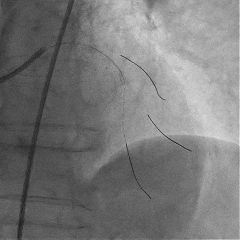

Sion导丝至LCX远端,预扩球囊扩张后,植入支架XIENCEAlpine 2.25*23mm支架一枚

术后造影支架膨胀良好,血流TIMI3级